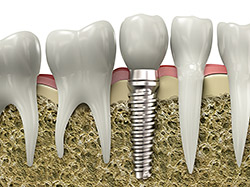

Implant restoration

If you have missing teeth, it is crucial to replace them. Without all your teeth, chewing and eating can destabilize your bite and cause you discomfort. When teeth are missing, your mouth can shift and even cause your face to look older. Implants are a great way to replace your missing teeth, and if properly maintained, can last the rest of your life.

An implant is a new tooth made of metal and porcelain that looks just like your natural tooth. It’s composed of two main parts: One is the titanium implant body that takes the place of the missing root, and the other is the tooth-colored crown cemented on top of the implant. With implant treatment, you can smile confidently, knowing no one will ever suspect you have a replacement tooth.

In addition to tooth replacement, implants may be used to anchor dentures, especially lower dentures that tend to shift when you talk or chew. For patients with removable partial dentures, implants can replace missing teeth so you have a more natural-looking smile.